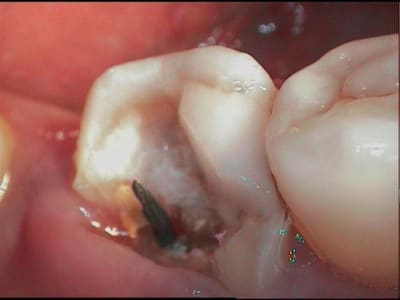

donc, immédiatement assainissement et prov rapide, et remission des signes en 15j

3 h14agw - Eugenol

4 sajz74 - Eugenol